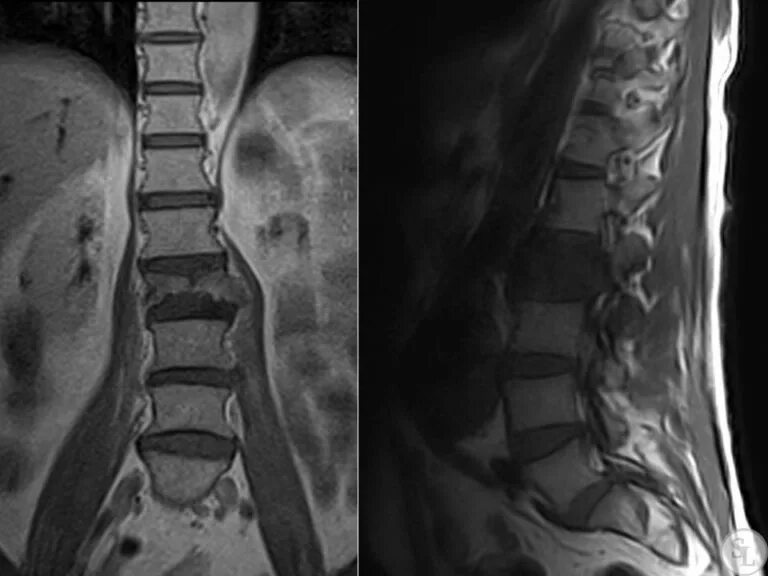

Метастазы в костном мозге